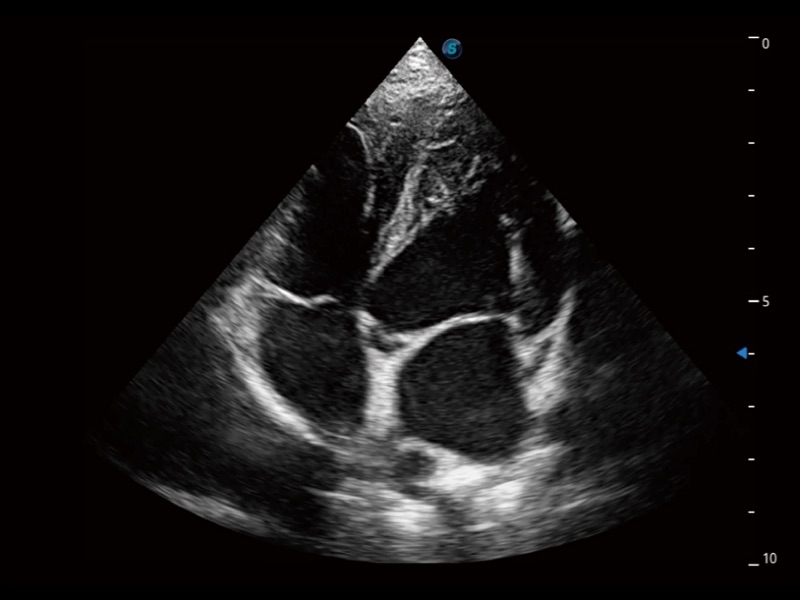

ProPet 70 进一步提升了微米成像算法,更加注重对基础原始图像的还原和保留,在有效减少斑点噪声、增强组织边界显示的同时,避免过度优化丟失真实的解剖信息。

能够基于左心室壁追踪和辛普森法,自动计算射血分数,支持多个可移动点描迹,与手动测量相比,极大节省了动物医生的时间和精力。

通过360度任意调节3条M型取样线,在同一心动周期上观察心脏不同位置的运动曲线,得到准确的心功能测量数据,有效评估心肌运动及左心室功能。

实时用颜色表示心肌组织运动,观察和定量组织的运动情况,对快速检测与评估心肌的灌注和活性、电传导及心肌收缩和舒张功能等均能提供重要的诊断信息。

当心脏测量结果超出正常范围时,可实时预警提示动物医生,减少疾病漏诊概率。